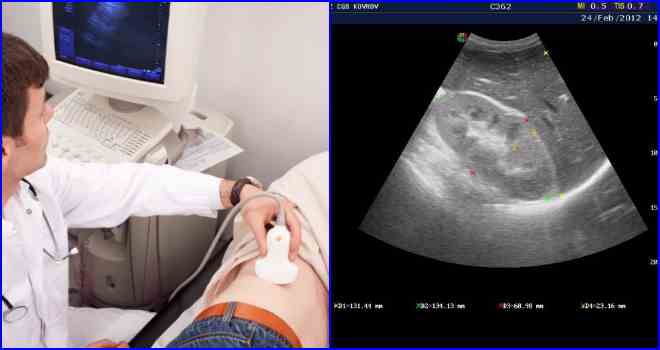

Ультразвукове дослідження нирок проводиться з метою діагностики патології і визначення стадії її розвитку.

На ультразвуковому дослідженні виявляються структурні зміни в нирках, які при розвитку цукрового діабету і підвищення концентрації глюкози в крові та сечі відчувають підвищене навантаження. Чим важче стадія захворювання, тим сильніше змінюється структура органу. Проводити дане обстеження необхідно 1 раз на рік, людям з наявністю генетичної схильності до захворювання — не менше 2 разів на рік.

Узд нирок часто виявляє патології, викликані обмінними порушеннями